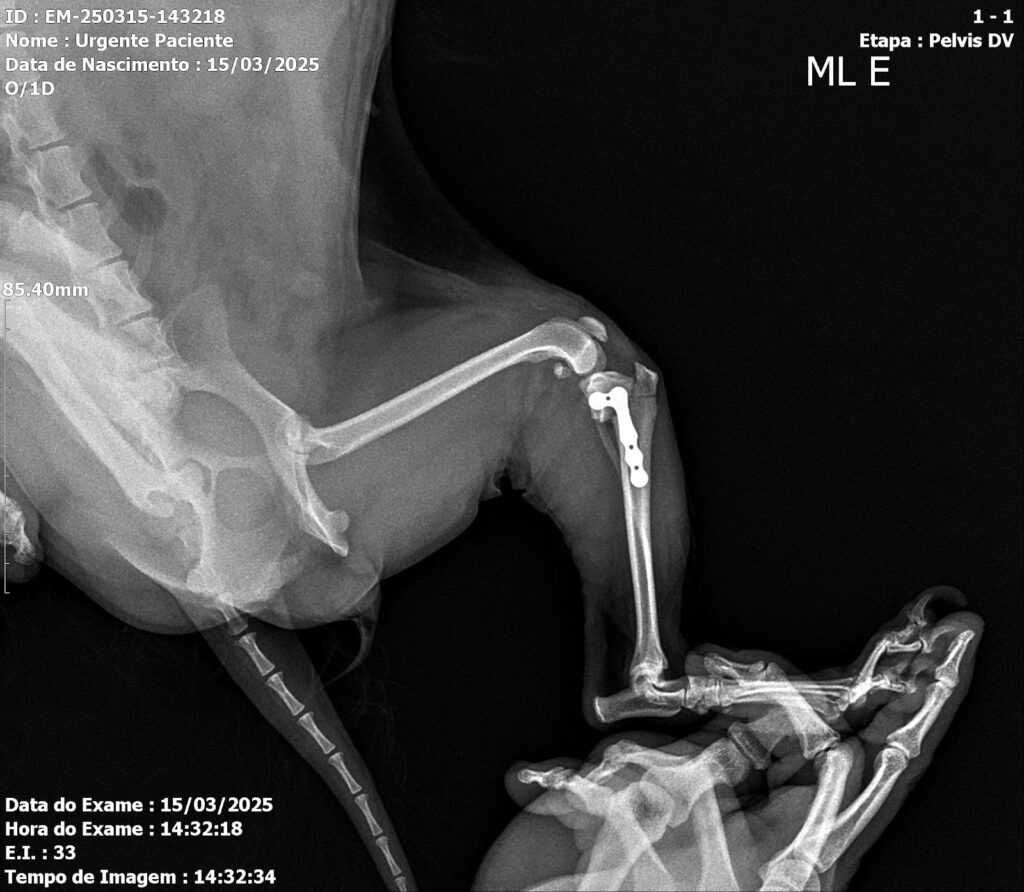

Postoperative evaluation included assessment of range of motion, limb alignment, and joint stability. Radiographs confirmed appropriate implant positioning and patellar alignment (Figures 4 and 5). A slight reduction of the medial femorotibial joint space was noted, with preservation of overall congruence. Mild lateral displacement of the patella was observed on the craniocaudal view and minimal caudal displacement on the mediolateral view. Increased soft-tissue opacity and volume, compatible with postoperative inflammatory changes, were also identified. The semicircular osteotomy in the proximal third of the left tibia and adequate implant positioning confirmed correct surgical execution.

Figures 4 and 5: Ventrodorsal and mediolateral radiographs of the left pelvic limb in the immediate postoperative period, showing fracture stabilization using an orthopedic plate and screws, with proper bone alignment.